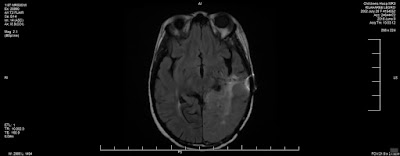

Dr. Manley considers today's MRI to be stable with some enhancements to the tumor area. For those unfamiliar with oncology's definition of enhancement, it is not the positive "increase or improvement in quality or value"...it is an increase in the size of the tumor area. The enhancements may be tumor growth or post-treatment changes (possibly from radiation). I suggested that it could also be from swelling caused by the Vitamin C.

When we compared June's MRI to today's, I could see the increase in size that he pointed out. Dr. Manley said that they will watch these areas closely. I asked if that means we will return to a 6-8 week MRI schedule. He thought we could continue to wait 10-12 weeks, but he said if I felt we needed one sooner that they could arrange that.

As I looked at the two pictures, I saw some areas that seemed to have more definition in the folds of her brain (where the tumor was previously filling in empty space). I asked Dr. Manley about it and he agreed that it did look better.

Dr. Manley said, "I treat people, not pictures." It reminded me of what Nurse Megan told us before March's MRI, "An MRI is just a picture." For those that want to see comparison pictures anyway, here they are...

August 24: